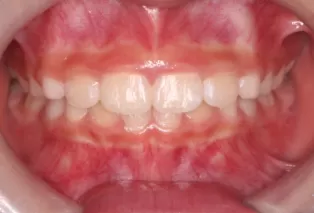

Photos intra-orales